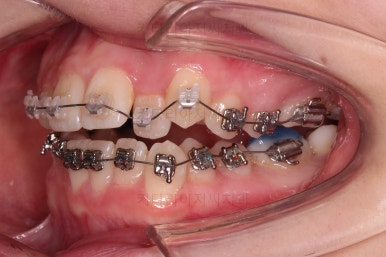

장치를 처음 부착한 사진입니다.

이번 환자분은 특징적으로 윗니의 장치와 아랫니의 장치가 다르죠.

윗니는 좀 더 심미적인 세라믹으로 선택하셨고 아랫니는 비교적 저렴하고 부피가 약간 작고 튼튼한 메탈로 진행했습니다.

비교적 조기에 앞니는 가지런해졌고요.

대신 교합이나 기울어진 느낌 등 디테일을 맞추기 위한 작업을 추후에 계속 하게 됩니다.